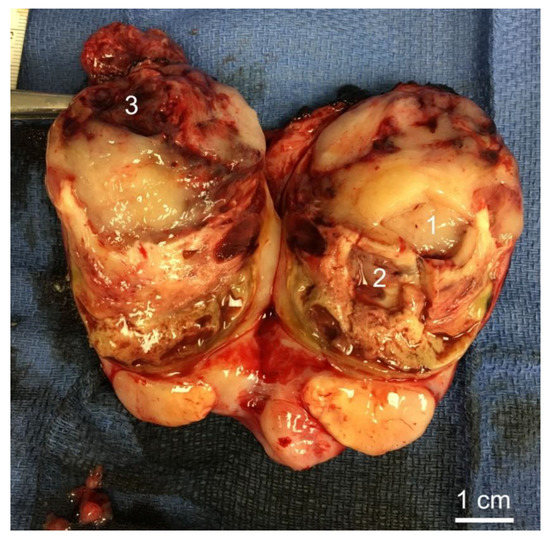

3.2. Histology of Biopsy Sites